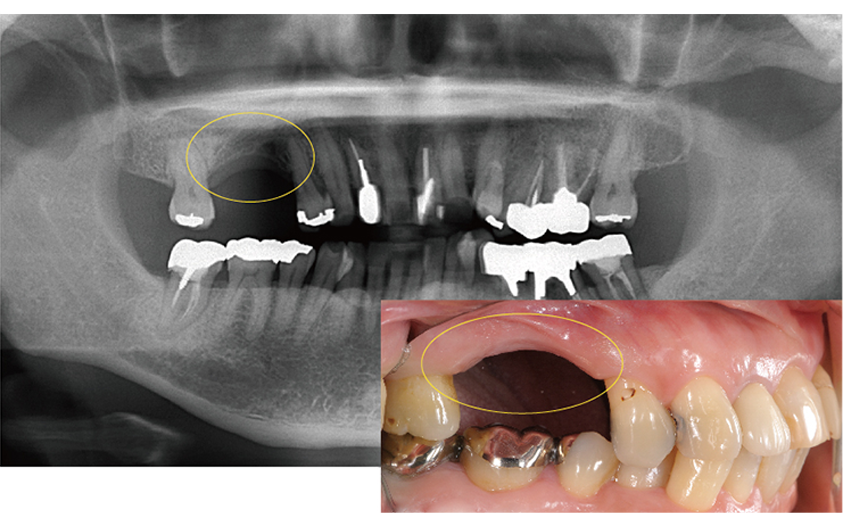

右下の奥歯が重度の虫歯で抜歯と診断。親知らずの移植を計画。

抜歯と同時に親知らずを移植

骨の再生が認められる

経過は良好

治療期間 6ヶ月

費用 15万円(歯の移植)

| メリット | 歯が生え変わったように自然な仕上がりで噛める |

|---|---|

| デメリット | 歯の移植は一度抜歯するため、生着しないことがある |

親知らずを移植したケース2

第二大臼歯のな根が折れており抜歯と診断

第一大臼歯がすでに欠損しているのでこのままだと奥歯が2本失ってしまう為、第二大臼歯に親知らずを移植し、第一大臼歯部はインプラント治療を計画した。

治療期間 1年

費用 60万円(インプラント45万 / 歯の移植15万)

| メリット | 親知らずを移植することでインプラントの本数を減らして費用を抑えることができる |

| デメリット | 歯の移植はインプラントに比べて成功率が低い |